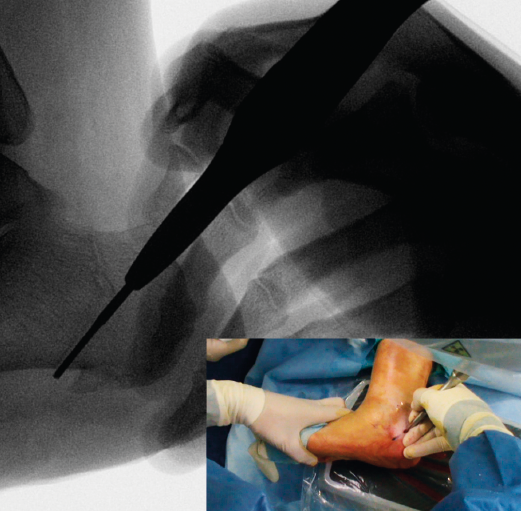

Figura 4. Imagen fluoroscópica de la fresa suelta introducida y su correspondencia en cirugía.

Ayudándose del mosquito para separar las partes blandas, se introduce una fresa Shannon 2 o 3 × 20 mm (FH Orthopedics, Mulhouse, Francia) en el vértice de la V. Comprobada la correcta posición de la fresa en la fluoroscopia (desconectando el motor de la fresa) (Figura 4), esta se avanza perpendicularmente al eje del calcáneo hasta atravesar la segunda cortical. Inclinando la fresa se pueden obtener diferentes desplazamientos, si bien, para conseguir un mayor desplazamiento, se recomienda avanzar perpendicularmente al eje. Si se quiere conseguir cierto efecto de descenso además de medialización de la tuberosidad se dirigiría la fresa en dirección de dorsolateral a plantomedial unos 15-30° respecto a la perpendicular del eje del calcáneo. Si lo que se quiere es obtener un efecto de elevación (beneficioso en el cavo posterior), la dirección sería la contraria, es decir, de lateroplantar a dorsomedial. Se podría obtener también acortamiento del calcáneo si la fresa se dirige de lateral distal a medial proximal, e incluso un alargamiento (de lateral proximal a medial distal), aunque esto último dificultaría el desplazamiento por la tensión de los tejidos(13).

Figura 5. Imagen fluoroscópica del trazo dorsal de la osteotomía y su correspondencia en cirugía.

La fresa se coloca en línea con el trazo de osteotomía dibujado en la piel, primero el dorsal y después el plantar (Figuras 5 y 6), y va cortando la pared lateral y el hueso esponjoso del calcáneo y progresando paulatinamente hasta alcanzar la segunda cortical y cortarla cuidadosamente. Se recomienda no superar en 6.000 rpm la velocidad de la fresa para evitar la osteonecrosis térmica. A pesar de que el procedimiento se realiza sin isquemia para que la sangre refrigere el calor de la fresa, se recomienda que el ayudante aporte suero salino para contribuir a tal efecto.

Figura 6. Imagen fluoroscópica del trazo plantar de la osteotomía y su correspondencia en cirugía.